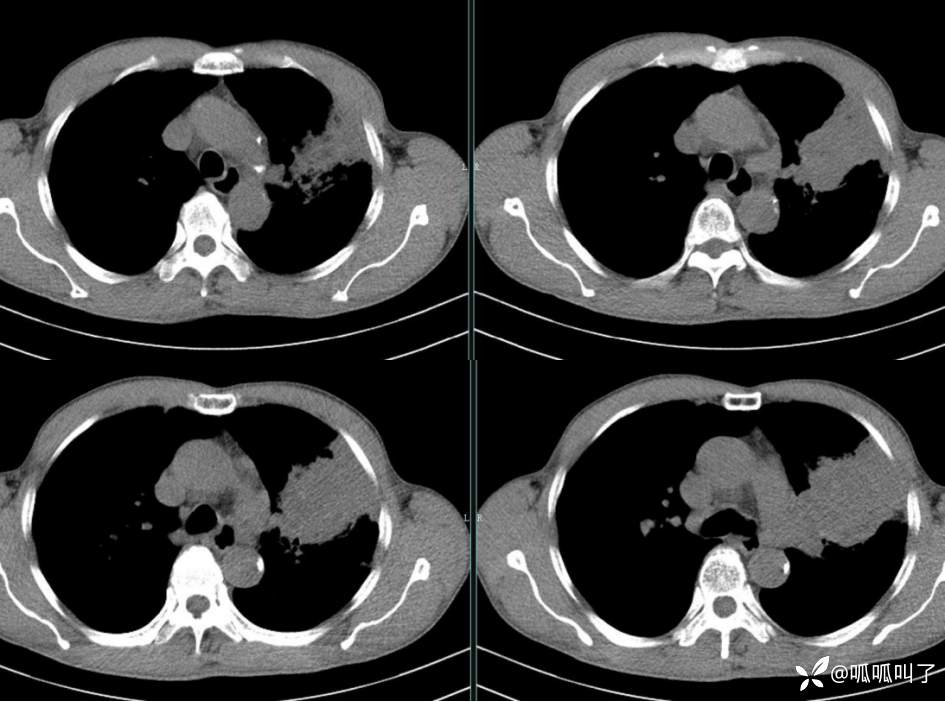

胸部CT平扫和增强: